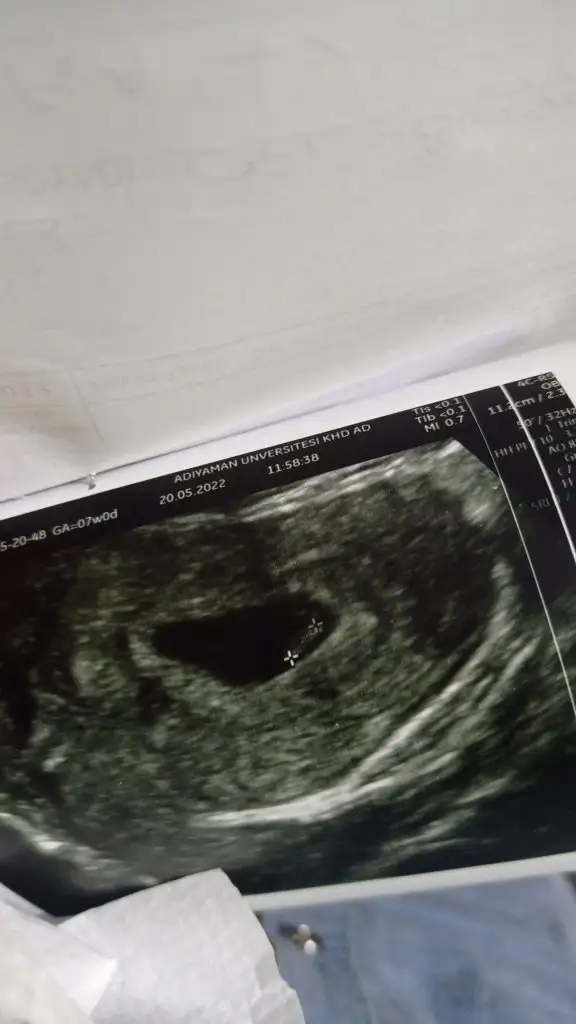

Merhaba bana ba bakabilir misiniz karından çekildi 6+3Can

Merhaba bana ba bakabilir misiniz karından çekildi 6+3